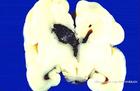

硬腦膜下積液的臨床表現酷似硬腦膜下血腫,亦有急性、亞急性和慢性之分,術前難以區別。其臨床特徵為輕型或中型閉合性頭傷,腦原發性損傷往往較輕,傷後有逐漸加重的頭疼、嘔吐和視乳頭水腫等顱內壓增高的表現。病程發展多為亞急性或慢性,偶而可呈急性過程。嚴重時亦可導致顳葉鉤回疝,約有30.4%的病人出現單側瞳孔散大,約半數有意識進行性惡化及錐體束征陽性。硬腦膜下積液量一般為50~60ml,多者可達150ml。其性狀,急性者多為血性腦脊液,稍久則轉呈黃色清亮液體,蛋白含量稍高於正常。